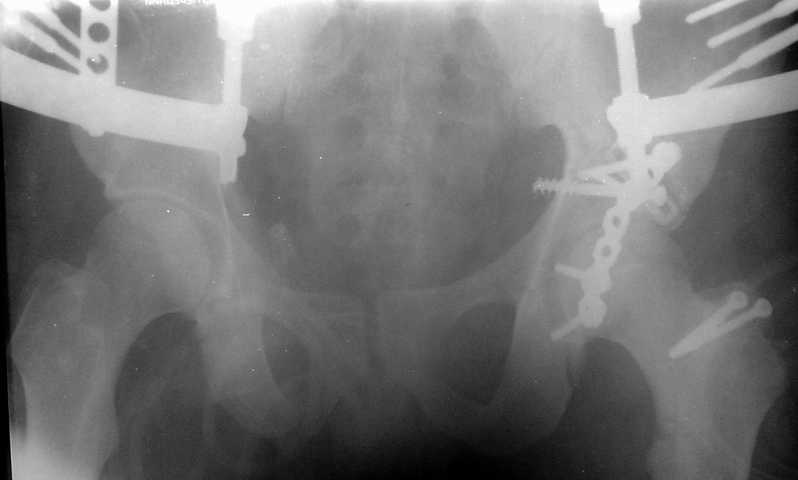

Травма 17 ноября 2002 г., поступил к нам 1 декабря, оперирован 8-го - открытая репозиция, остеосинтез пластинками и винтами. Учитывая повреждение переднего полукольца справа, и крестца и крестцово-подвздошного сочленения слева, наложили аппарат на 2 месяца.

Для экономии места привожу интра- и послеоперационный обзорный снимок, без дополнительных проекций.